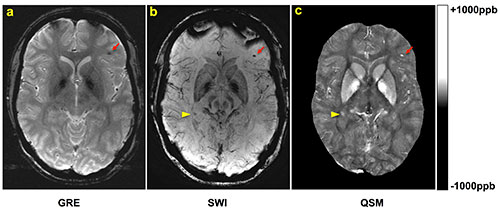

Wei Liu, D.Sc., of Walter Reed National Military Medical Center, and colleagues studied 603 military personnel patients who underwent two-dimensional conventional gradient-recalled-echo MR imaging and three-dimensional flow-compensated multiecho gradient-recalled-echo (GRE) MR imaging (processed to generate susceptibility-weighted images [SWI] and quantitative susceptibility maps [QSM]), and a subset of patients who underwent follow-up imaging. Microhemorrhages were identified by two radiologists independently. Comparisons of microhemorrhage number, size, and magnetic susceptibility derived from quantitative susceptibility maps between baseline and follow-up imaging examinations were performed by using the paired t test.

Among the 603 patients, cerebral microhemorrhages were identified in 43 patients, with six excluded for fur­ther analysis owing to artifacts. Seventy-seven percent (451 of 585) of the microhemorrhages on susceptibility-weighted images had a more conspicuous appearance than on gradient-recalled-echo images. Thirteen of the 37 patients underwent follow-up imaging examinations. In these patients, a smaller number of microhemorrhages were identified at follow-up imaging compared with base­line on quantitative susceptibility maps (mean ± standard deviation, 9.8 microhemorrhages ± 12.8 vs. 13.7 microhe­morrhages ± 16.6; P = .019). Quantitative susceptibility mapping–derived quantitative measures of microhemor­rhages also decreased over time: -0.85 mm3 per day ± 1.59 for total volume (P = .039) and -0.10 parts per bil­lion per day ± 0.14 for mean magnetic susceptibility (P = .016).

A, gradient-recalled-echo (GRE), B, susceptibility-weighted imaging (SWI), and, C, quantitative susceptibility mapping (QSM) images in a patient with traumatic brain injury.